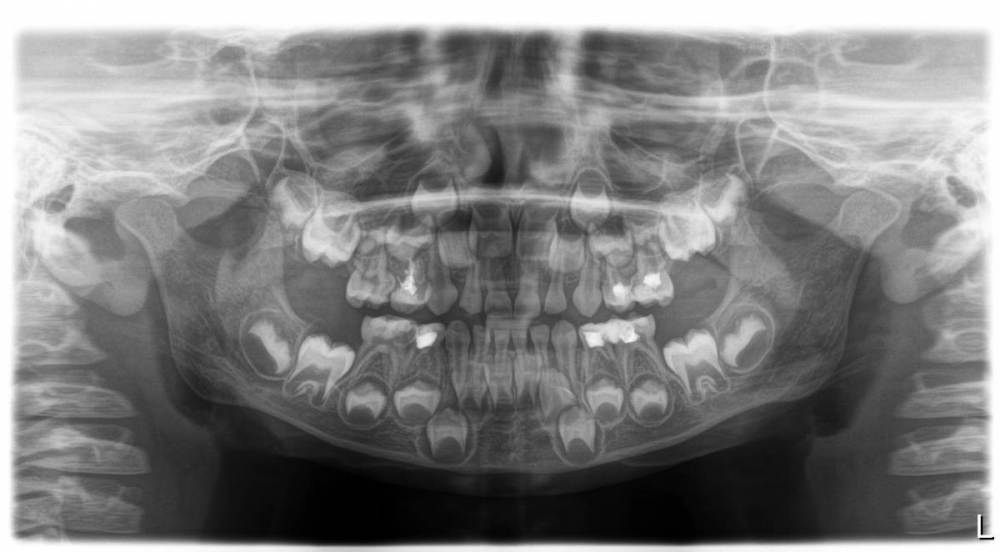

Пациенту 4 года 9 месяцев, боли нет.

74-75 лечили повторно, поставить постоянную пломбу ребенок не дал, сейчас под временной пломбой.

Возможно ли спасти 74 зуб?

На какие зубы необходимы коронки?

оптг.jpg